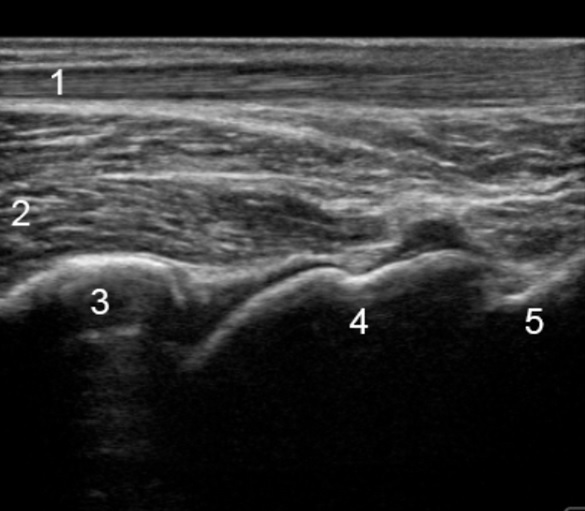

Foot & Ankle Posterior Ankle Longitudinal 2 Image

1. Achilles

2. Flexor Hallucis Longus

3. Tibia

4. Talus

5. Calcaneus